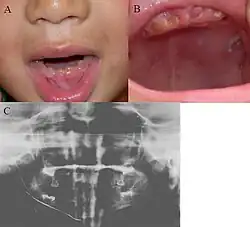

| Oral photographs from an individual with Dentinogenesis imperfecta | |

People with this condition have abnormal enamel, short and narrow roots, and can lack nerves. This condition can cause teeth to be discolored (most often a blue-gray or yellow-brown color) and translucent, giving teeth an opalescent sheen.[2][3][8][5][9] Teeth are also less mineralized than normal, making them prone to rapid wear, breakage, and loss.[2][3][4][5][8] These problems can affect primary (baby) teeth alone, or both baby teeth and permanent (adult) teeth, with the primary teeth usually more severely affected.[5][8]

- Discolored teeth - teeth may be amber, brown, blue or opalescent

- Bulbous shape to the tooth crown due to cervical constriction

- Tooth wear/Non-carious tooth surface loss (NCTSL) - due to the poorly mineralized dentin, the enamel of the tooth is unsupported and subsequently shears or chips off as it is subjected to occlusal (biting) forces. This exposes the underlying less mineralized dentin which is less resistant to wear. Therefore, features of abrasion and attrition may become apparent.

The primary (baby) teeth are usually more severely affected than permanent (adult) teeth.[3][5][8]

Enamel is usually lost early because it is further inclined to attrition due to loss of scalloping at the dentinoenamel junction (DEJ). It was suggested that the scalloping is beneficial for the mechanical properties of teeth as it reinforces the junction between enamel and dentin.[15] However, the teeth are not more susceptible to dental caries than normal ones.

Radiographic presentation

Radiographic features include:

- Bulbous shape of tooth crown with pronounced cervical constriction

- Small pulp, or total pulp obliteration

- Small or obliterated root canal

- Presence of pulp stones

- Narrow and small roots

- Periapical radiolucency without any evidence of clinical pathology such as tooth decay (dental caries)[2][3][5][14]